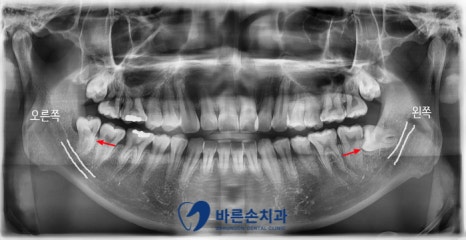

안녕하세요. <의정부 바른손치과>입니다.! 오늘은 사랑니 발치 증례를 보여드리도록 하겠습니다. 이 환자분은 20대 중반의 남성분으로 양쪽 아래 사랑니가 아프셔서 발치를 하러 저희 바른손치과를 찾아주셨습니다. 엑스레이 사진에서 보시면 양쪽 위 아래 사랑니가 모두 있고 왼쪽 아래 사랑니가 누워서 부분적으로 매복되어 있는 상태입니다. 구강 내 사진입니다. 좌우 모두 사랑니 머리가 일부만 구강내로 맹출해있습니다. 이런 경우 음식물이 끼기 쉽고, 칫솔로 제거도 쉽지가 않습니다. 그래서, 잇몸이 부어 피가 나고 아픈 경우가 자주 일어 날 수 있고 나아가 앞에 있는 치아 까지 썩게 할 수 있습니다ㅜㅜ 이런 경우엔 사랑니 발치를 통해 구강 환경 개선을 해야합니다!!! 사랑니 발치에 앞서 3D CT 촬영을 하였습니다. 사랑니의 형태와 위치, 아래턱뼈에 있는 하치조신경관의 해부학적 위치를 정확히 확인 후 발치에 들어갑니다. 오른쪽 아래 사랑니를 발치하고 엑스레이를 찍어 확인하였습니다. 왼쪽아래 옆으로 누워있는 사랑니도 발치를 하였습니다. 환자분께서는 문제를 일으키던 사랑니를 뽑으니 홀가분하고 시원하다고 하셨습니다.!! 약 일주일 정도 회복기간을 가지시면 사랑니 부위의 잇몸은 어느정도 아물게 됩니다. 사랑니 발치 더이상 두려워 하지 마시고 <의정부 바른손치과>에서 뽑으세요^^ |